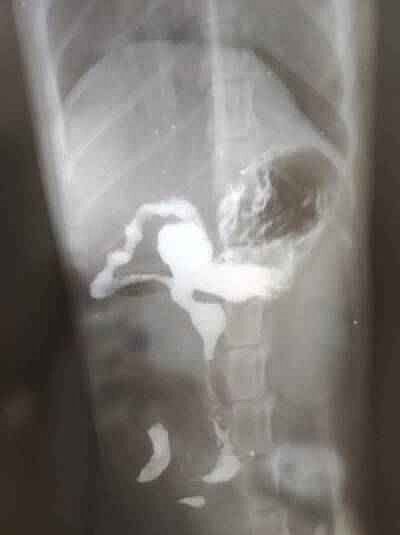

только пришли. сделали рентген, на снимке непроходимость в верхнем отделе кишечника, на выходе из желудка.

иначе вечером прооперируют после контрольного снимка.

влили 25 кубиков контраста, он имеет хорошие обволакивающие свойства, а значит есть шанс. что до вечера этот злосчастный комок может сдвинуться по кишечнику.

очень похоже. что это кляп из шерсти. как я и предполагала

вот что ответил один из хирург-эндоскопист

’Добрый день, судя из рентгеновских снимков, непроходимость у животного наблюдается в тонком отделе кишечника. В таком случае эндоскопическое вмешательство не показано, оно используется только для извлечения инородных тел полости желудка’

вот наш рентген. вдруг кто-то разбирается? нам через два чаа на повторный рентген и тогда уже будет совсем мало времени для маневра. Если этот затор не сдвинулся от контраста, скорей всего сразу под скальпель